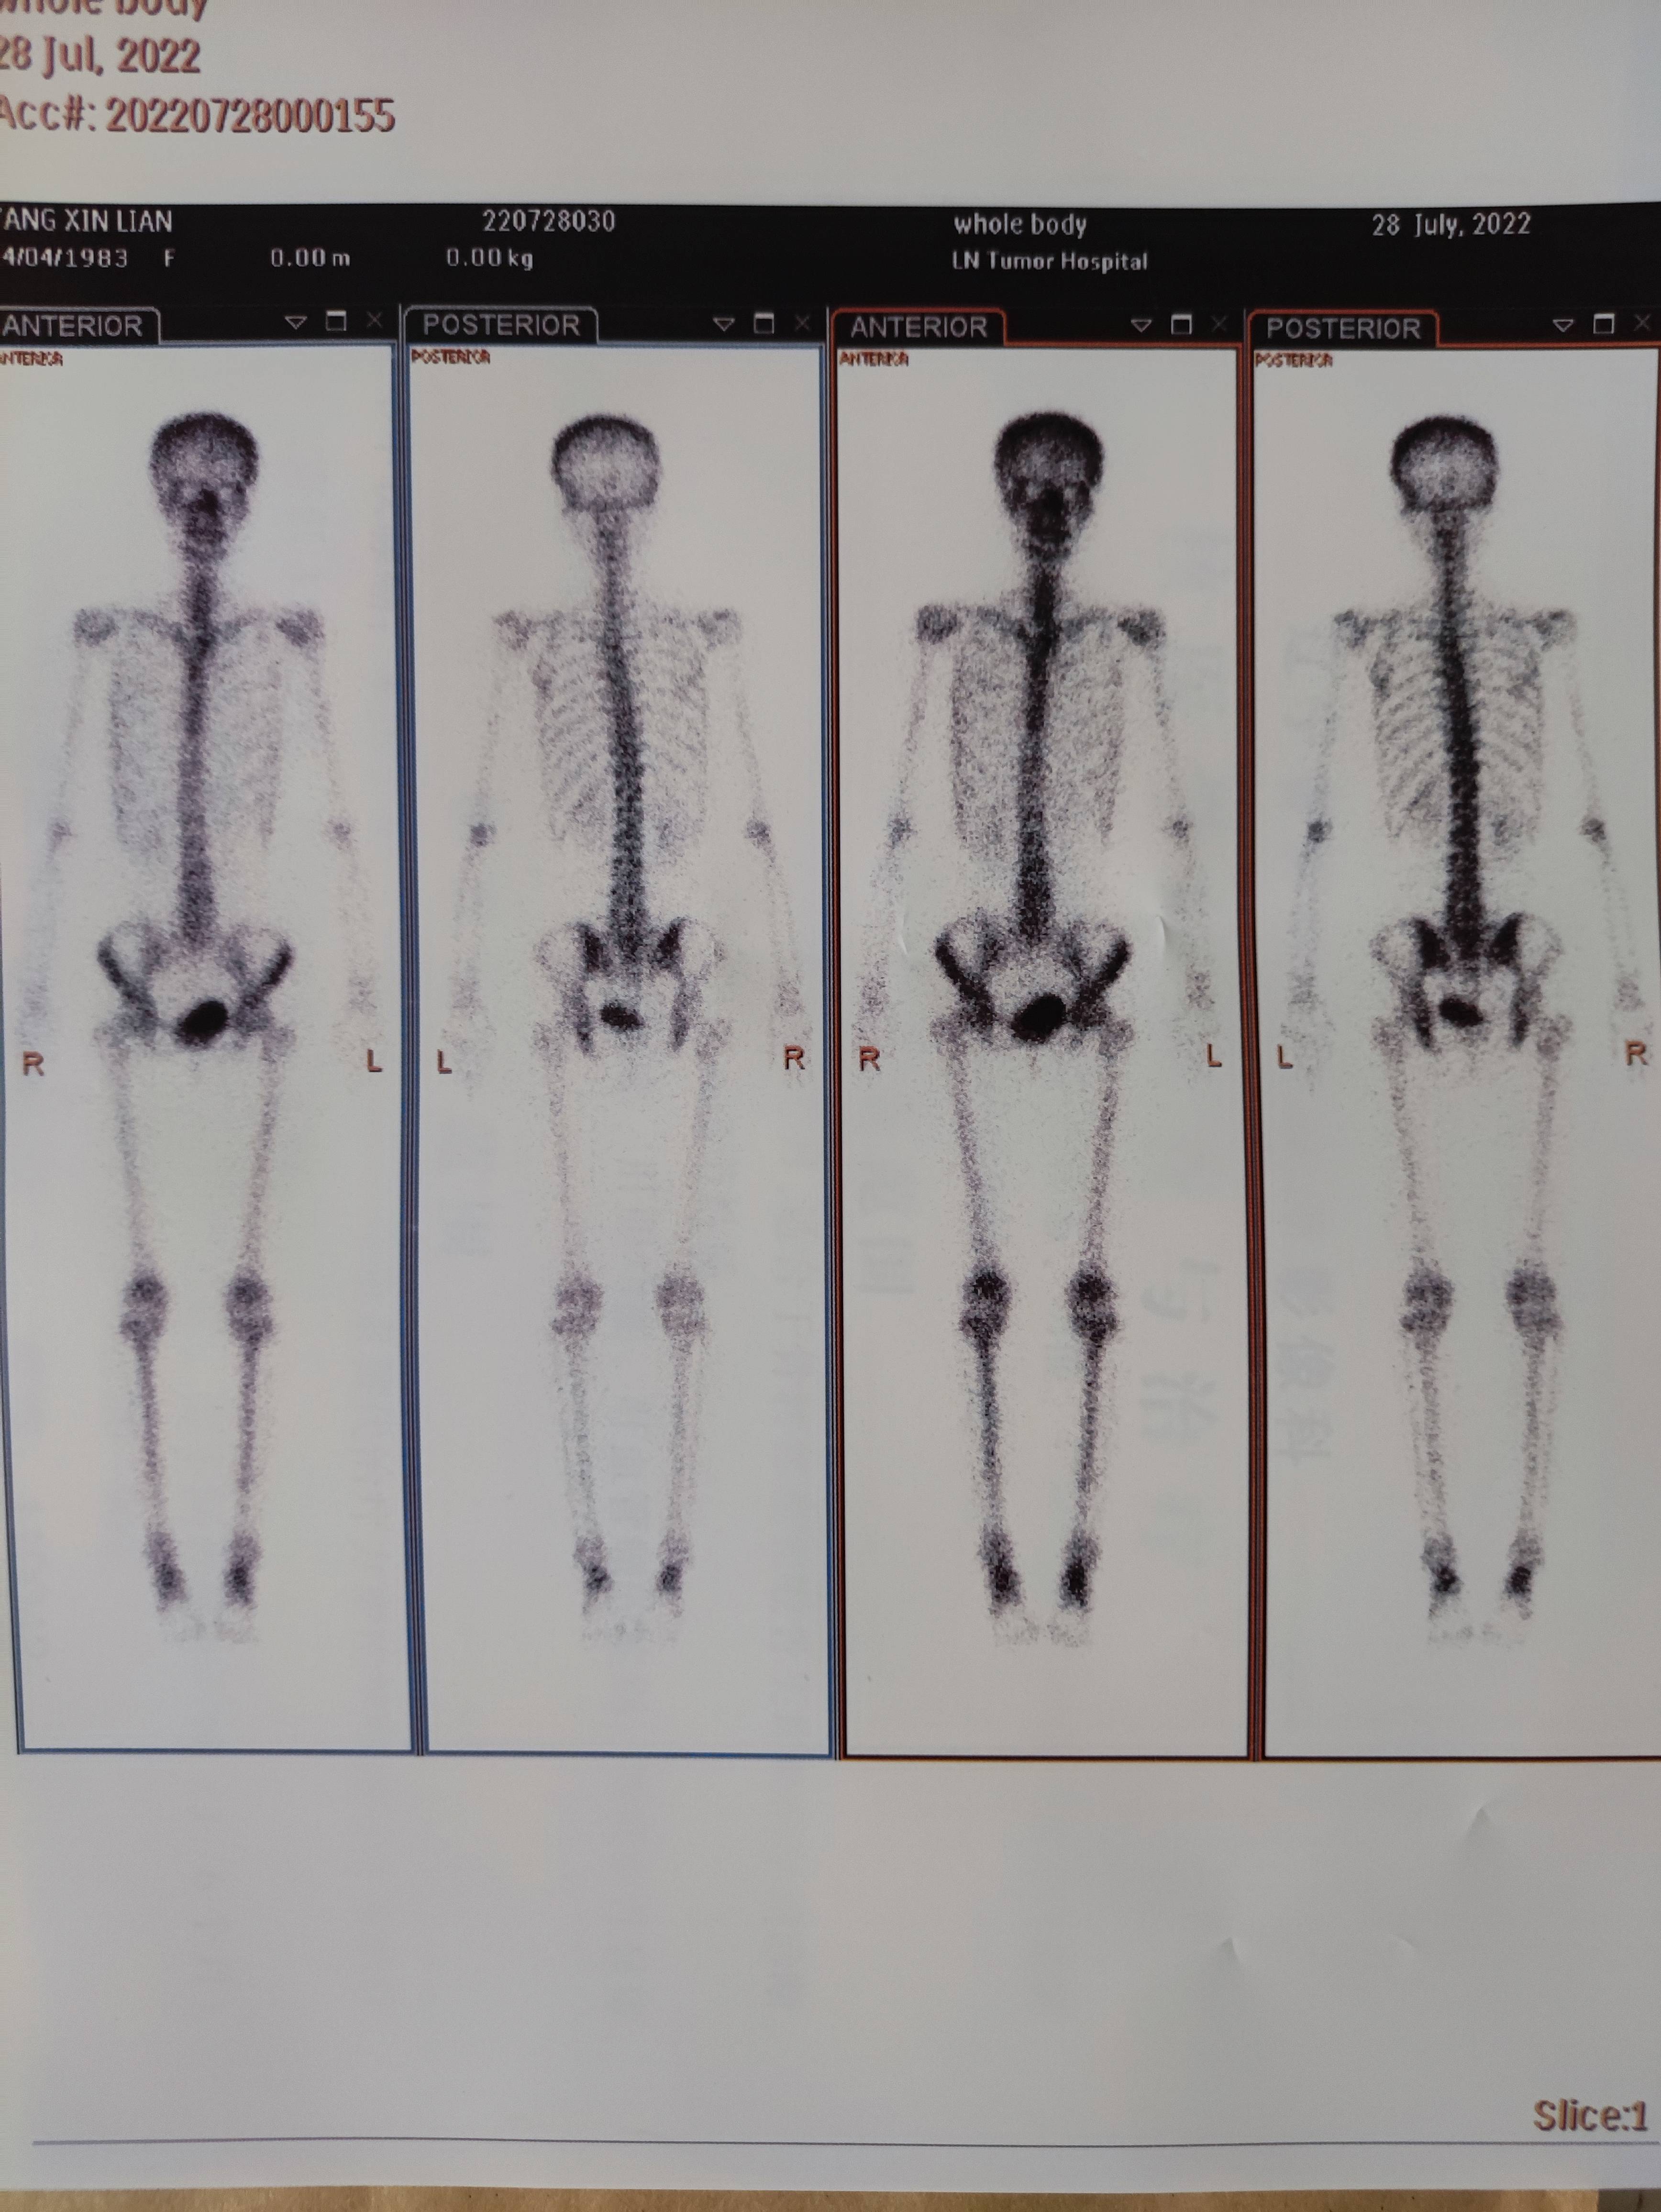

这是我有史以来拍过最恐怖的照片

自2019年确诊乳癌至今没做过骨扫描,上个月月底去医院大复查,医生的意思已经2年半了,应该做了,我也想做吧放心。当天做完骨扫描一个小时后手机就出结果了,报告提示是正常骨像,医生那边也能通过电脑查询结果,就一直没取片子。昨天下午去医院开药顺便取回来片子,我在整理检查单子时顺便打开看了一眼,嘛呀这不就是一具💀吗,虽然知道骨扫描当然是给骨头拍照,可看到眼前自己这幅样子还是吓了一跳,觉得好恐怖😱😱😱😱